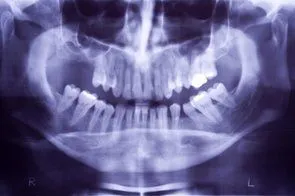

Ridge Augmentation

When you lose teeth, and do not replace them, the jawbone deteriorates where the tooth socket once was. This makes it difficult, and in some instances impossible to get dental implants or dentures later on. You may have not had the financial means at the time of the extraction for restorative surgery, but you may have the money now. The good news is that we can perform a process called ridge augmentation to restore the bone structure that is needed for restorative procedures such as dental implants. The process involves lifting the gum from the ridge to expose the defected area of the bone. Then the dentist uses a bone like substance to fill the defected areas. The ridge augmentation greatly improves the appearance of the mouth and increases the chances for success with the implants. With ridge augmentation, your implants will last for years.